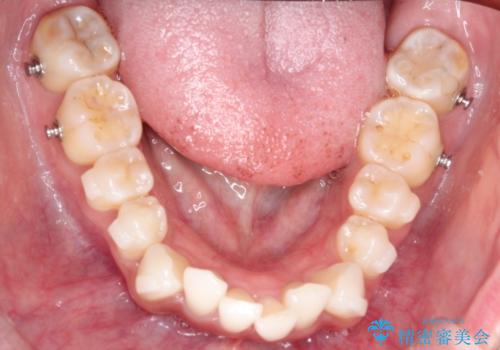

精密検査の結果、歯を並べるためのスペースが不足していましたが、抜歯をせずに改善したいというご希望があったため、IPR(歯の側面をわずかに削る処置)と、奥歯を後ろに動かす「遠心移動」を組み合わせる計画を立案。透明なマウスピース装置であるインビザラインを使用し、無理のない範囲でスペースを確保しながら歯列を整えることとしました。

治療では、マウスピースの設計に基づき、奥歯から順に後ろへ移動させる遠心移動を行い、前歯のためのスペースを作りました。同時に、数箇所の歯の間にIPRを施すことで、歯の健康に影響のない範囲で精密に隙間を確保しました。

1年半の治療期間を経て、重なり合っていた前歯はスムーズに整列し、理想的なアーチ状の歯並びへと改善されました。抜歯を行わずに治療を完了したことで、噛み合わせのバランスを維持しながら、審美性を大きく向上させることができました。現在は保定期間に入り、美しい状態を維持されています。